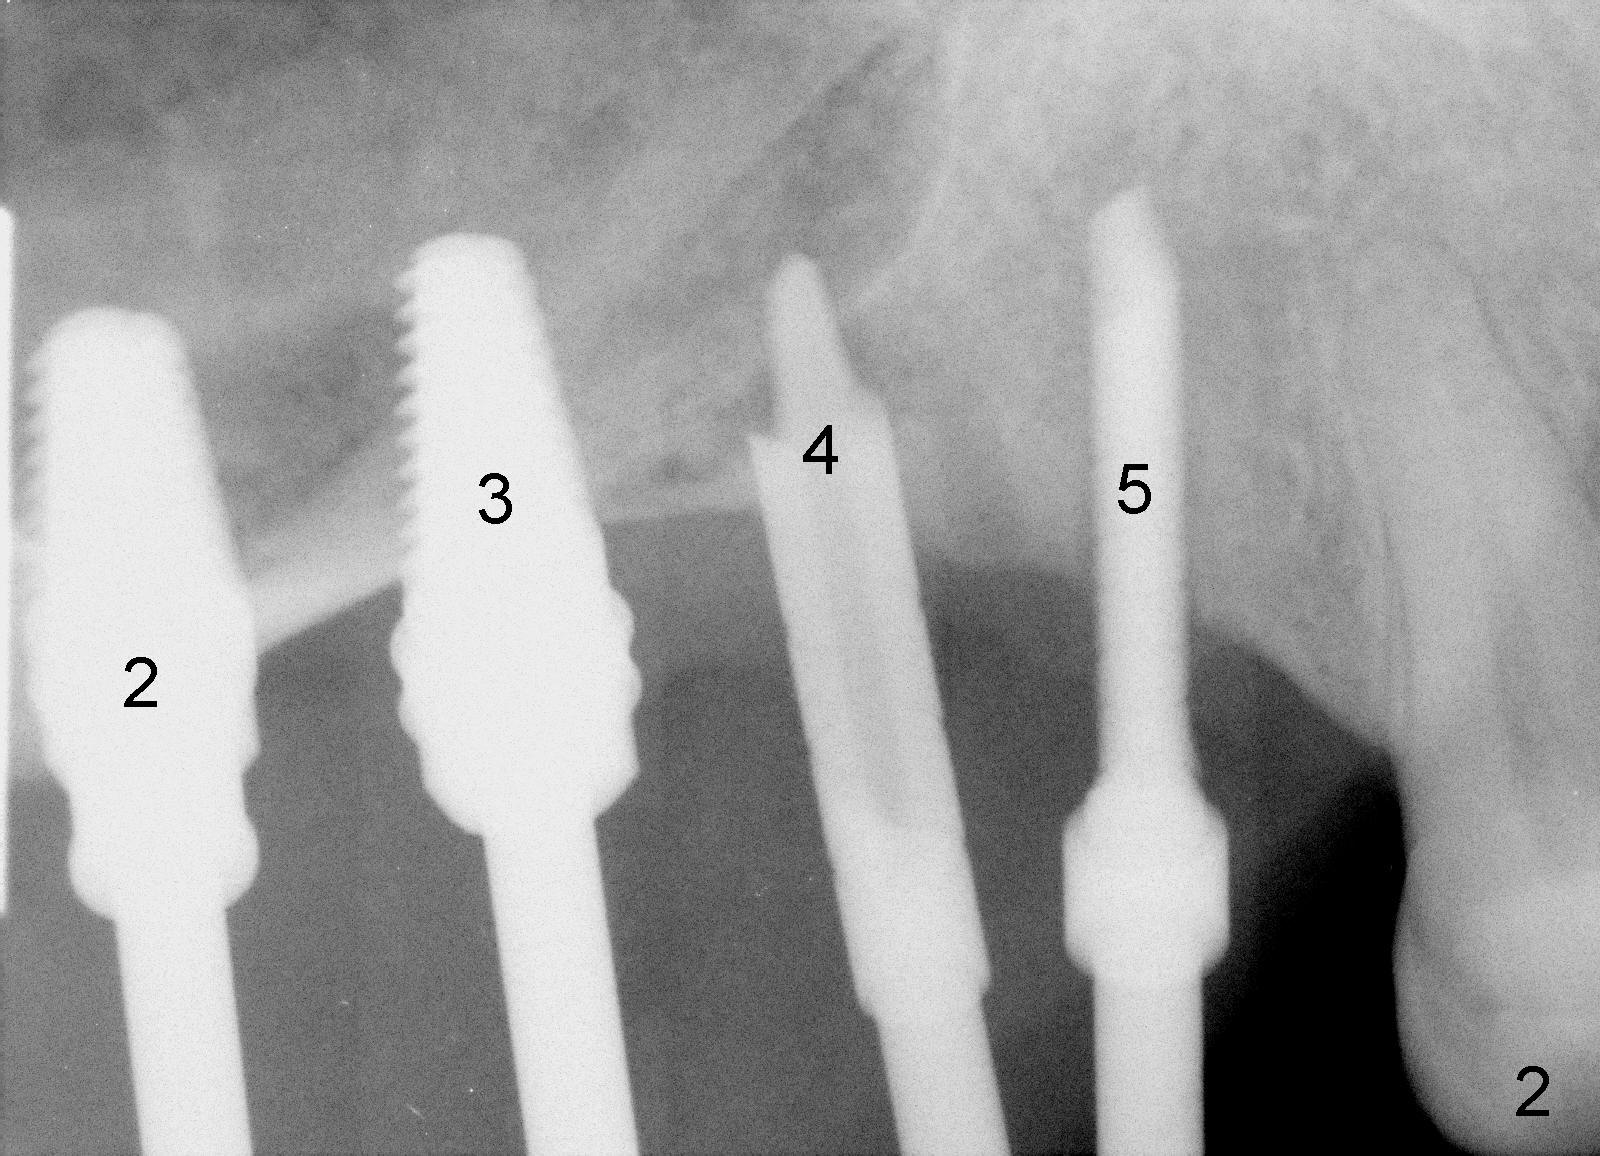

When the sinus membrane is lifted, osteotomies are made at the sites of #2-5 (Fig.2) with insertion of taps at #2 and 3 and reamers at #4 and 5.

A 3.5x17 mm one-piece implant is placed at #5 and a 4x11 mm two-piece at #4 with crack line buccally (Fig.3 <), while a 4.5x11 mm tap is in place at #3.

Fig.4 shows 4 implants in place with implant apex sticking into the sinus (>, which will be covered by bone graft). Fig.5 is a PA taken post bone graft, while Fig.6 is a section of panoramic X-ray showing the boundary of bone graft (arrowheads) after cementation of a provisional bridge. The latter satisfies the patient's request for cosmetics.